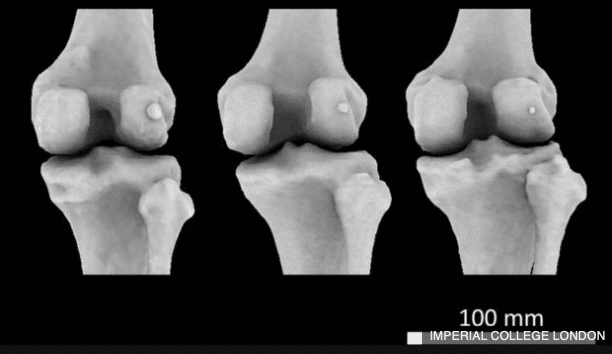

Fabella on pieni siemenen muotoinen jänneluu, joka sijaitsee ihmisellä polven alueella. Sitä tavattiin aiemmin ihmisen kädellisillä esivanhemmilla.

Brittiläisen Imperial College London -yliopiston tekemän tutkimuksen perusteella luu on nyt 3,5 kertaa yleisempi kuin vuosisadan alussa. Vuonna 1918 luu esiintyi 11,2 prosentilla väestöstä, sata vuotta myöhemmin noin 39 prosentilla väestöstä.

Tutkimusryhmän mukaan muutokset luustossa voivat perustua polvilumpion kasvaneeseen rasitukseen, sillä ihmiset ovat nykyään paremmin ravittuja eli korkeampia ja raskaampia kuin ennen. Apinoilla Fabellan on tutkittu toimivan toissijaisena polvilumpiona ja lisäävän tarvittaessa polven mekaanista voimaa sekä vipuvoimaa.